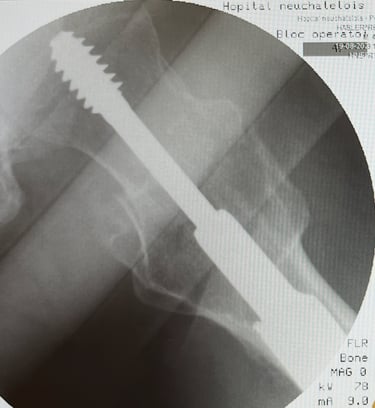

Diagnosi e trattamento delle patologie dell’anca, incluse artrosi, tendinopatie e traumi.

Terapie conservative, infiltrative e chirurgiche, inclusa chirurgia protesica d’anca.